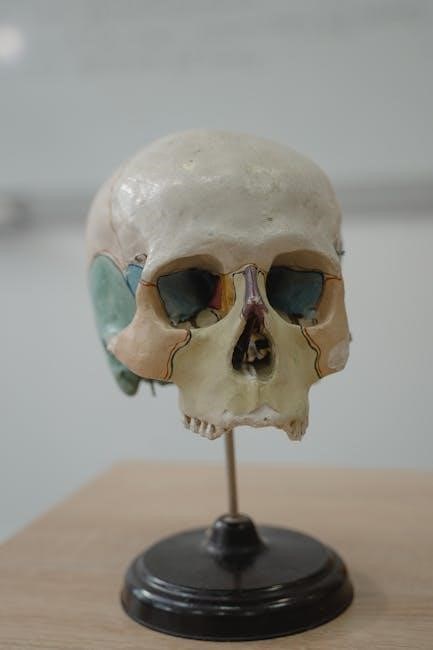

Anatomy and Physiology study guide PDFs dedicate significant sections to the skeletal system, detailing its crucial roles. These guides explore bone composition – including compact and spongy bone – and classifications based on shape: long, short, flat, irregular, and sesamoid. They illustrate bone structures like epiphyses, diaphyses, and articular cartilage.

Functionally, these resources emphasize support, protection of vital organs (like the skull safeguarding the brain), assistance in movement via muscle attachment, mineral storage (calcium and phosphate), and blood cell formation (hematopoiesis) within bone marrow.

PDF guides often include detailed diagrams of specific bones – femur, humerus, vertebrae – and joints – synovial, cartilaginous, fibrous – explaining their range of motion and stability. Clinical correlations, such as fractures, osteoporosis, and arthritis, are frequently included to demonstrate the practical application of anatomical knowledge. Understanding skeletal anatomy is foundational for grasping overall body mechanics and potential pathologies, making it a core component of any comprehensive Anatomy and Physiology study resource.